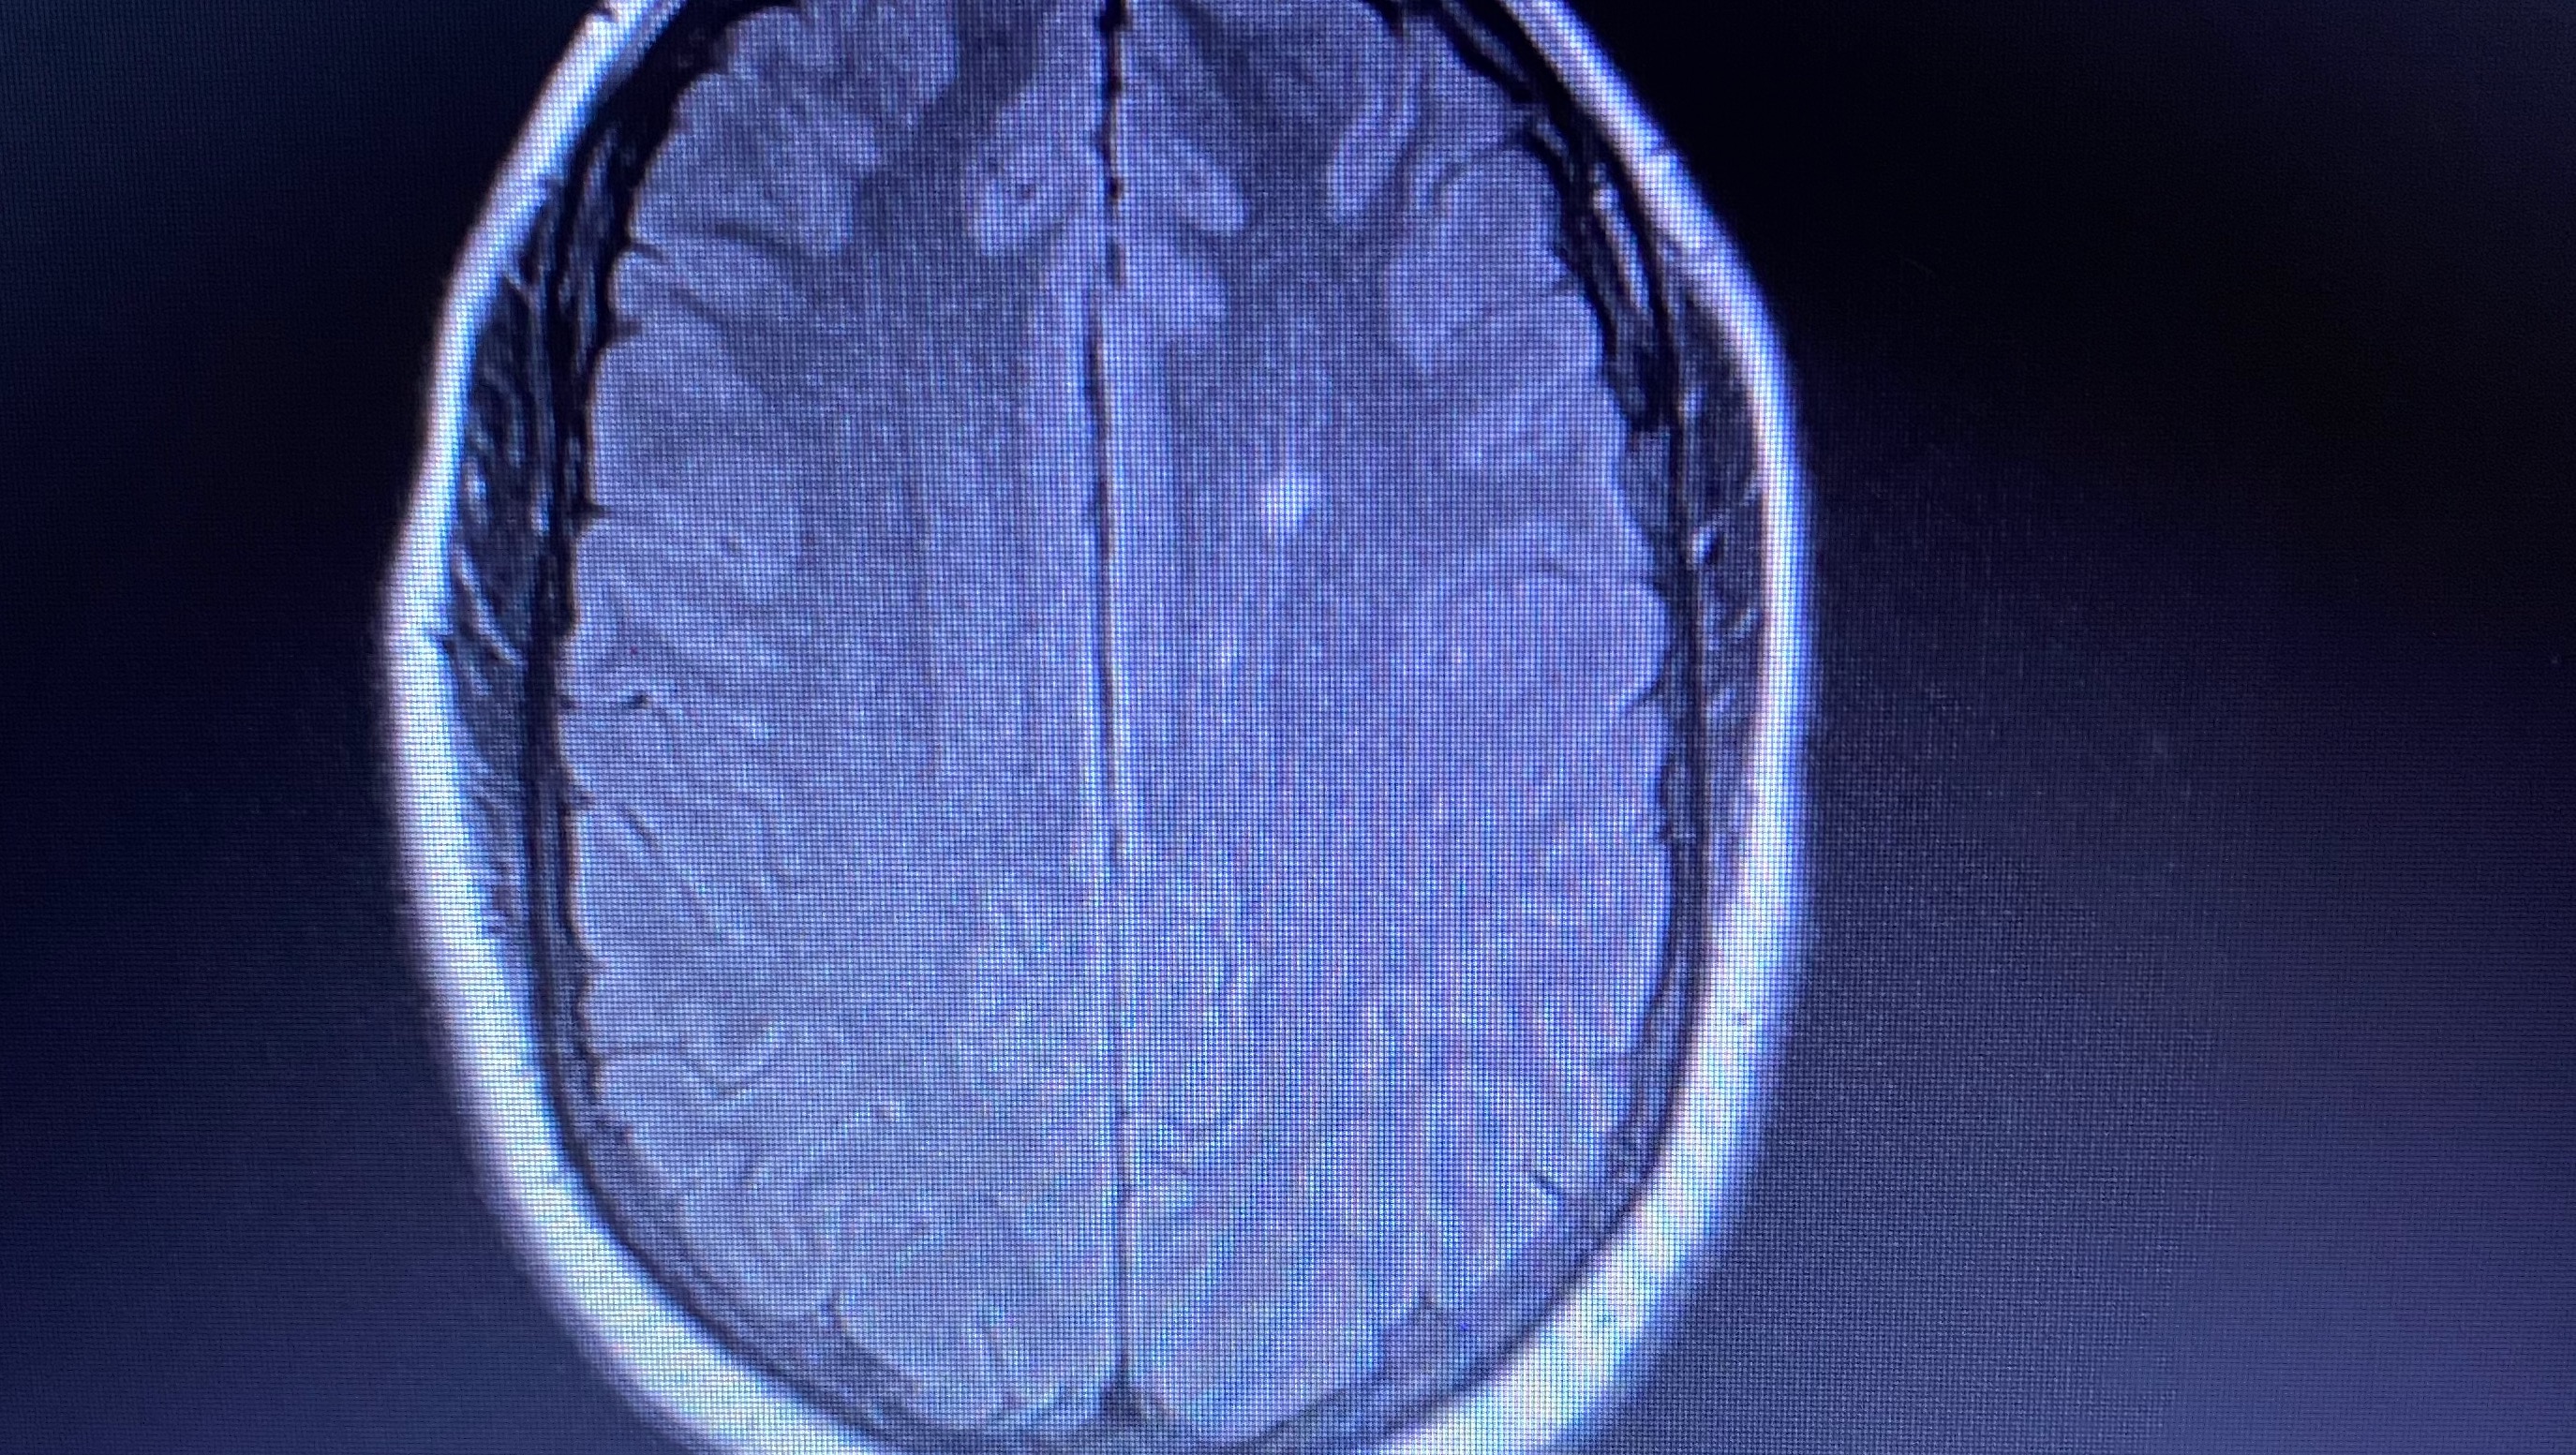

Hello, my name is Cortney. Usually, I’m not one to ask for any type of help. However, due to recent life events, my life has been tossed and thrown upside down. I am usually the one who is always giving help when needed and this time I’m on the other side. It has been 2 weeks since I’ve been able to work and unfortunately I am in the process of being diagnosed with 2 autoimmune diseases. Unfortunately, at this time I do not know when or if I’ll be able to return to work to be able to take care of my son as well as myself, as the doctors and neurologists are still sending me for testing and treatments and infusions. The worry of bills have become a reality.